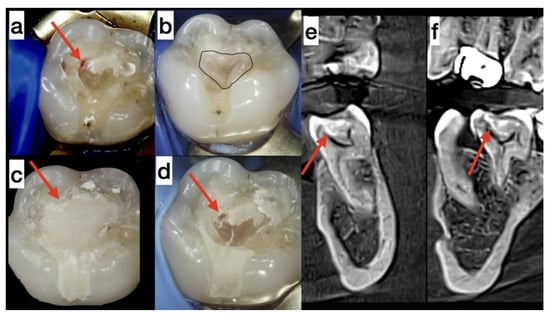

Case 1. A 47-year-old woman was diagnosed with reversible pulpitis observed in tooth 36 (electropulp test [EPT]: 11 µA, Scorpion, Optica Laser, Sofia, Bulgaria; saturation 82%; Contec CMS 8000D, Qinhuangdao, China). The carious lesion was located on the occlusal surface of the tooth. During the excavation of caries, the lesion was found to communicate with the dental pulp near the mesiolingual pulp corn by approximately 1 mm, with minimal bleeding (Figure 1a). For this treatment, the patient signed a standard informed consent. In addition, due to the use of platelet concentrate, the patient also signed an informed consent to administer A-PRF+. Direct pulp capping was performed using A-PRF+ in accordance with Choukroun’s protocol [9,10].

Under anesthesia, pulp wound hemostasis and cavity disinfection with ozone gas was performed for 24 s using an ozone generator (Prozone, TIP TOP TIPS Sarl, Rolle, Switzerland) [13]. Venous blood (10 mL) was obtained from the patient by venipuncture and centrifuged at 1300 rpm for 14 min (Duo Centrifuge/Process for PRF, Nice, France). An A-PRF+ membrane was made from blood plasma and applied to the pulp wound (Figure 1b). The volume of the inserted membrane was large and filled a significant part of the cavity. The pulp wound was covered by only an A-PRF+ membrane. Above this membrane, MTA cement (Angelus, Londrina, Brazil) was applied to fix the A-PRF+ membrane to the dentin. The calcium silicate cement had no contact with the pulp communication. Therefore, the healing effect on the pulp was from its contact with A-PRF+. The cavity was closed with glass ionomer cement (GIC; Fuji LC II, GC Int. Corp, Tokyo, Japan) (Figure 1c). The patient complained and reported spontaneous pain for several minutes during the next two days without needing medication.

After the resorption of the platelet concentrate, a gap formed since the membrane volume was significant (Figure 1b). Therefore a second visit was required. Under the magnification of an operating microscope, the temporary restoration was carefully removed. A newly formed dental bridge was observed under sterile conditions. The dental pulp was intact (Figure 1d). There was no pain during probing or percussion. On the second visit, there was no observable communication with the pulp. Therefore, we used indirect pulp capping by placing calcium silicate cement—Biodentine (Septodont, Saint-Maur-des-Fossés, France) and a definitive composite restoration (Diamond, Kulzer, Hanau, Germany). In the sixth month after the beginning of the treatment, the tooth was asymptomatic, with an EPT result of 16 µA and a saturation value of 83% [14].

At the sections of CBCT, the formation of a dentin bridge was observed at the site of pulp communication (Figure 1e,f red arrows). The volume of the dental pulp was maintained (the orifices of the mesiolingual and distal root canals were preserved) (Figure 1f). Near the mesiobuccal orifice, the formation of excess reparative dentin was observed. This may attribute to the elevated electric pulp testing values after six months at the tender points in the mesiobuccal cusp. The method for assessing the vitality of the dental pulp comprises measuring its blood circulation. We used a pulse oximeter and dental probes to measure blood circulation. The results obtained showed normal blood circulation (84–83%) from the first until the last day of the examination period, even though the EPT values increased (from 6 to 16 µA) [14].

Figure 1. (a) Cavity without carious dentin—the red arrow indicates the communication with the dental pulp. (b) Application of A-PRF+ membrane on the pulp wound. (c) Application of a glass ionomer cement. (d) The communication with the pulp was covered by reparative dentin three months later. (e) Cone beam computed tomography (CBCT) of tooth 36 after treatment at the coronal section—the red arrow indicates dentin bridge. (f) CBCT of tooth 36 after treatment of the sagittal section—the red arrow indicates dentin bridge.